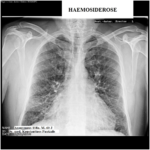

Ἡ ἀκτινογραφία θώρακος (εἰκ.2) ἔδειξε στοιχεῖα διαμέσου πνευμονικῆς ἰνώσεως (δικτυοοζώδης σκίαση) ἐντοπιζομένης κυρίως στὰ μέσα καὶ κατώτερα πνευμονικά πεδία ὑπὸ τὴν ἔννοιαν τῆς παρουσίας περιβρογχικῶν καὶ περιαγγειακῶν ἰνώσεων. Τοῦ συνέστησα περαιτέρω κλινικοεργαστηριακὸ ἔλεγχο. Μετὰ τρίμηνο ὁ ἀσθενὴς ἐπανῆλθε προσκομίζοντας τὴν τελικὴ διάγνωση τοῦ Νοσοκομείου Νοσημάτων Θώρακος << Σωτηρία>> καὶ ἡ ὁποῖα ἦταν ἰδιοπαθὴς πνευμονικὴ αἱμοσιδήρωση.Ὁ ἀσθενὴς μᾶς ἐπεσκέφθη ἔκτοτε ἄλλες δύο φορὲς τὸ 2018 (εἰκ.4) καὶ τὸ 2021 (εἰκ. 5), φαινεται δὲ ὅτι ἡ παθολογικὴ ἀκτινολογικὴ εἰκόνα ἐκ τῶν πνευμόνων δὲν ἔχει οὐσιωδῶς μεταβληθεῖ.

Διάγνωση: Βασίζεται στὴν ἀξιολόγηση τοῦ ἱστορικοῦ καὶ τῆς κλινικῆς ἐξετάσεως ἰδία κατὰ τὴν διάρκεια ὀξέων ἐπεισοδίων τῆς νόσου, ὅπου ὁ γιατρὸς στὴν ἀκρόαση μπορεῖ ν’ ἀκούσει ἕνα λεπτὸ κροτάλισμα ἢ κουδούνισμα στὸ τέλος τῆς εἰσπνοῆς. Ὁ ἔλεγχος τῆς πνευμονικῆς λειτουργίας δείχνει περιοριστικὴ ἀναπνευστικὴ διαταραχὴ κατὰ τὴν διάρκεια ἑνός ὀξέος ἐπεισοδίου τῆς νόσου. Ὁ αἱματολογικὸς ἔλεγχος ἀποκαλύπτει σιδηροπενικὴ ἀναιμία. Στὰ ἀκτινολογικὰ εὑρήματα ἑνὸς ὀξέος δυσπνοϊκοῦ ἐπεισοδίου διακρίνει κανεὶς αὔξηση τῆς πνευμονικῆς σκιερότητος στὸ ἐπίπεδο τῶν βρογχιολίων –κυψελίδων ἄνοδο τῶν διαφραγμάτων, σὲ χρόνια δὲ διαδρομὴ τῆς νόσου διακρίνεται δικτυοοζώδης εἰκόνα τοῦ πνευμονικοῦ παρεγχύματος λόγω ἀναπτύξεως διαμέσου πνευμονικῆς ἰνώσεως, διεύρυνση τῶν πνευμονικῶν πυλῶν καὶ μεγαλοκαρδία ἐκ τῆς συνυπαρχούσης πνευμονικῆς ὑπερτάσεως. Ἡ τελικὴ διάγνωση τίθεται μὲ τὴν βρογχοσκόπηση, βρογχοκυψελιδικὴ ἔκπλυση καὶ βιοψία.